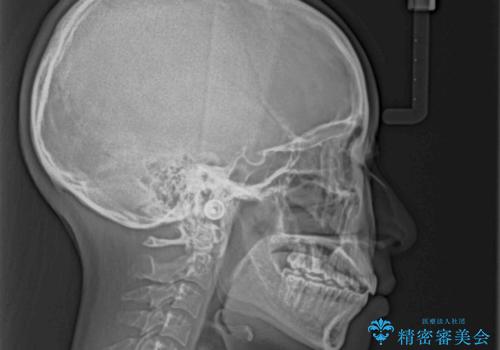

前歯にデコボコがあり、口元がやや突出した印象があったため、IPR(歯と歯の間を削る)と親知らずを抜歯した上での歯列全体の後方移動をメインに、インビザラインを用いて矯正治療を行うこととしました。